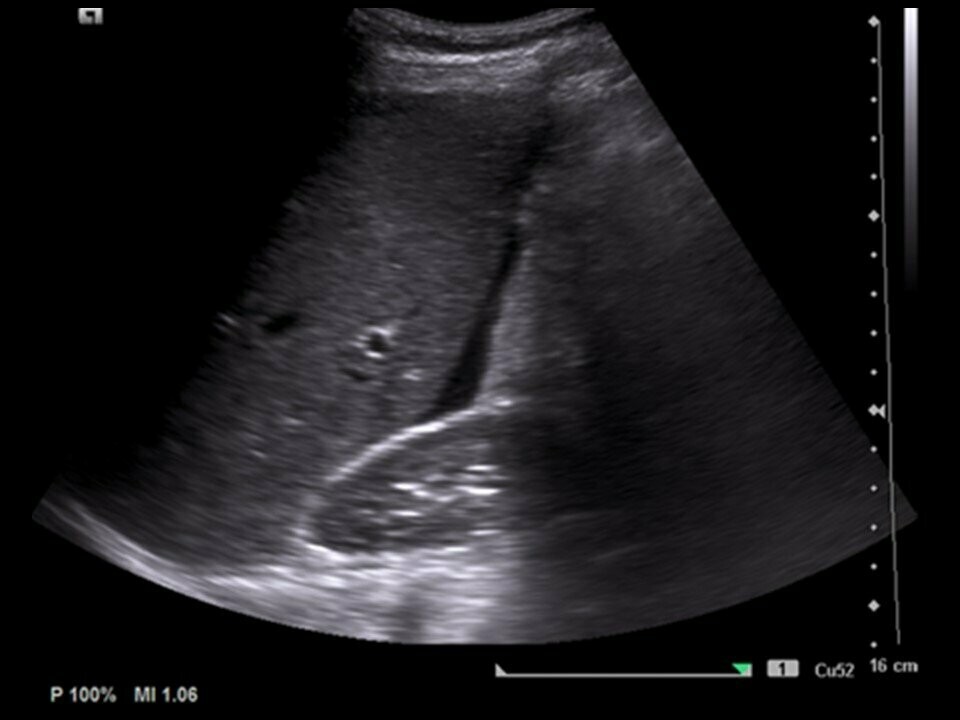

Imagenes de ultrasonido abdominal general YouTube

Source: www.youtube.com